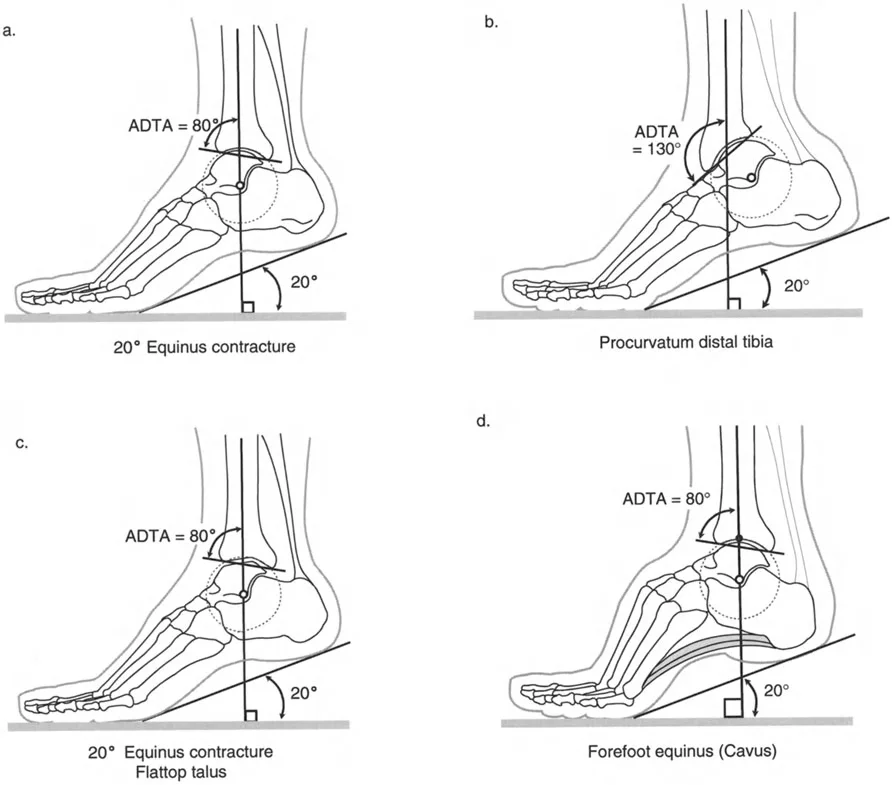

زاوية الكاحل الظهرية الظنبوبية (ADTA)

تُستخدم زاوية الكاحل الظهرية الظنبوبية (ADTA) كمعيار تشخيصي مهم لتقييم مدى تقوس الكاحل. وهي تقيس الزاوية بين محور عظم الظنبوب ومستوى عظم الكاحل. في الوضع الطبيعي، تسمح هذه الزاوية بحركة كافية لثني القدم للأعلى. أي انحراف عن هذه الزاوية الطبيعية يمكن أن يشير إلى وجود تقوس أو تشوه.

- تقلص الكاحل (Ankle Contracture): يحدث هذا عندما تكون الأنسجة المحيطة بالمفصل (المحفظة والأربطة) مشدودة، مما يحد من حركة المفصل دون وجود تشوه في العظام نفسها.

- صورة توضح تقلصًا في الكاحل بزاوية 20 درجة.

- تقوس الظنبوب البعيد (Procurvatum of Distal Tibia): في هذه الحالة، يكون هناك انحناء غير طبيعي في الجزء السفلي من عظم الظنبوب، مما يمنع عظم الكاحل من الثني للأعلى بشكل طبيعي بسبب اصطدامه بالظنبوب.

- عظم الكاحل المسطح (Flattop Talus): يحدث هذا عندما يكون الجزء العلوي من عظم الكاحل مسطحًا بدلاً من شكله المستدير الطبيعي، مما يؤدي إلى اصطدامه بعظم الظنبوب عند محاولة ثني القدم للأعلى.

- القدم الجوفاء (Cavus Deformity) أو تقوس مقدمة القدم (Forefoot Equinus): في هذه الحالة، يكون قوس القدم مرتفعًا بشكل غير طبيعي، وقد يؤدي ذلك إلى تقوس ثانوي في الكاحل بسبب اختلال توازن العضلات والأوتار.

- صورة شعاعية توضح تقلصًا في الكاحل بزاوية 20 درجة.